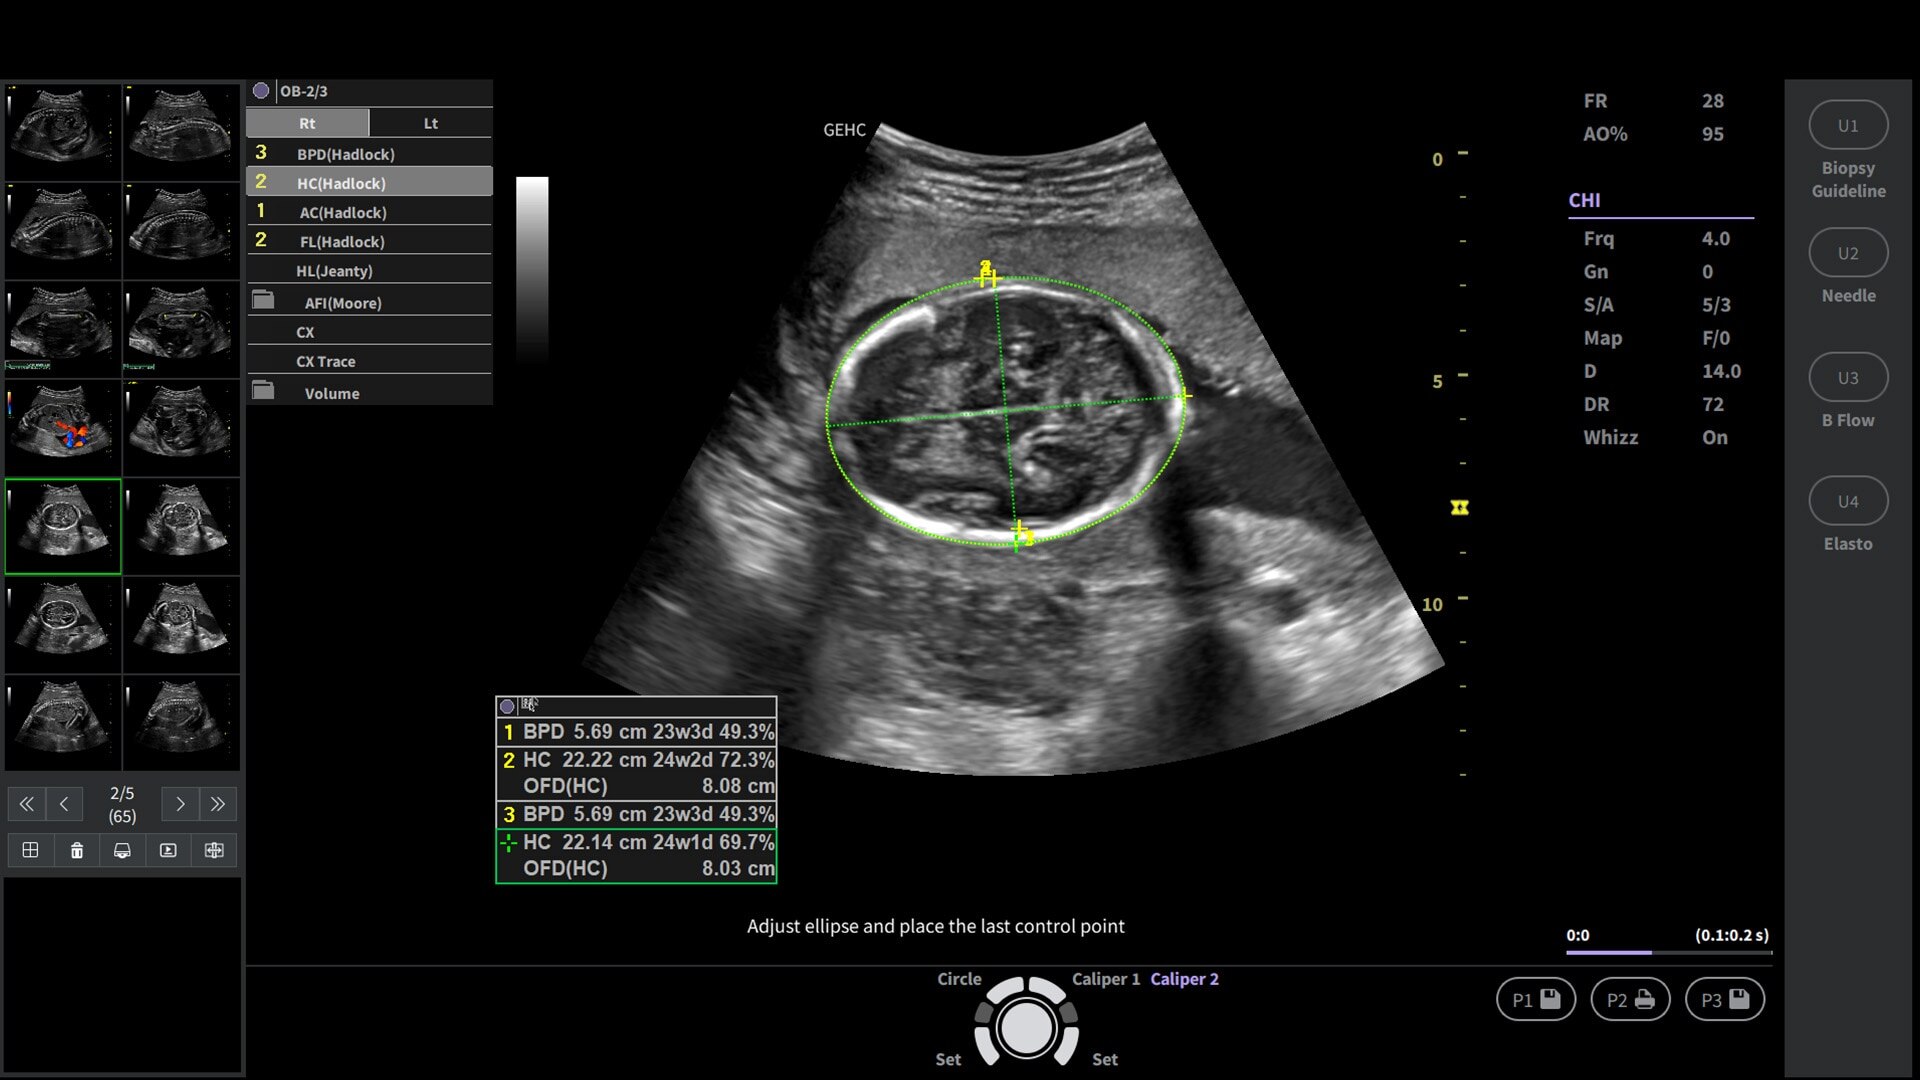

Powered by VisionBoost Architecture, Versana Premier provides optimal image quality so users can easily reach a diagnosis. Advanced clinical features help address challenging cases while automated tools help reduce scan time:

• Optimize images while scanning with Whizz clinical features, easily improve Color Doppler with Whizz Color Flow, and view scans in the image style that suits your preference with Whizz Easy Style

• Make automated 2D Measurements and Volume Calculations with Auto Contour, Auto Bladder, Whizz Follicle and Auto-IMT

Support OB scanning with faster 3D/4D rendering and capture incredible static 3D/4D imaging